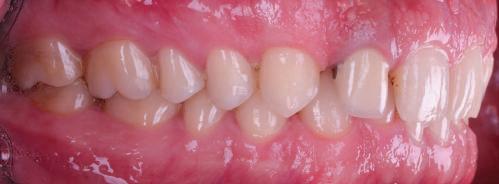

7Dental Tribune Bulgarian Edition / октомври 2022 г. Преди лечението Фиг. 1 Фиг. 4 Фиг. 7 Фиг. 10 Фиг. 13 Фиг. 16 Фиг. 17 Фиг. 18 Фиг. 19 Фиг. 20 Фиг. 11 Фиг. 14 Фиг. 12 Фиг. 15 Фиг. 8 Фиг. 9 Фиг. 5 Фиг. 6 Фиг. 2 Фиг. 3

8 Dental Tribune Bulgarian Edition / октомври 2022 г. По време на лечението Фиг. 21 Фиг. 25 Фиг. 30 Фиг. 31 Фиг. 34 Фиг. 38 Фиг. 40 Фиг. 44 Фиг. 48 Фиг. 50 Фиг. 49 Фиг. 46 Фиг. 39 Фиг. 41 Фиг. 45 Фиг. 47 Фиг. 42 Фиг. 43 Фиг. 35 Фиг. 36 Фиг. 37 Фиг. 32 Фиг. 33 Фиг. 26 Фиг. 28 Фиг. 29 Фиг. 27 Фиг. 22 Фиг. 23 Фиг. 24

9Dental Tribune Bulgarian Edition / октомври 2022 г. След лечението За авторите: Д-р Манол Ивчев е създател на COLDY DENT Functional Atelier, завършва дентална медицина във ФДМ, София. Шест години е стажант в ортодонтска практика. Интересите му са изцяло насочени към функционалната дентална медицина. Посещава курсовете на Доусън и Льо Гал. Преминава редица обучения, акредитирани от Института на Славичек във Виена – VieSID. Впоследствие става най-младият инструктор във VieSID. Придобива права да преподава философията на проф. Рудолф Славичек в България. В практиката си се придържа към протоколите на Славичек за функционално лече ние и диагностика, тъй като те са насочени към комплексно лечение. Завършва всички нива за морфология на зъбите и моделаж при Janos Mako. Повишава знанията си по функционална ортодонтия чрез индивидуален курс в Румъния. Д-р Ивчев е и сертифициран зъболекар по лингвална ортодонтия от Катедрата по ортодонтия от Университета по стоматология в Тегу, Южна Корея. Сертифициран е и за лечение на ортодонтски аномалии чрез миофункционални апарати, а също и за ортодонтия, подпомагана от миниимпланти, отново от Университета по стоматология в Южна Корея. Завършва индивидуално обучение по функционална ортодонтия в Университета по дентална медицина в Богота, Колумбия, както и индивидуално обучение по функционална ортодонтия и физиотерапия по про токола на Mariano Rocabado. Има завършено индивидуално обучение по функционална зъботехника и функционален Wax-Up клас I,II и III. Завършва курс за Digital Smile Design и Skin Concept в Люксембург при Christian Coachman, Florin Cofar, Paulo Kano, Josef Kunkela, Livio Yoshinagа. Зт. Leandro Gambogi, Бразилия, завършва зъботехника през 1999 г. Експерт и пионер в дигиталната диагностика. Лектор и инструктор на курсове в областта на дигиталното протезиране. Понастоящем е главен изпълнителен директор и зъботехник в DENTALE DIGITAL LAB. В периода януари 2005 г. – декември 2006 г. завършва бизнес управление и администрация в Methodist University Center Izabela Hendrix. Съавтор на книгата Odontologia Digital: Desafiando os Limites, глава 5: „Дигитално включване във времето. Технология CAD/CAM“. Преминал множество обучения при световноизвестни кли ницисти. Фиг. 51 Фиг. 54 Фиг. 57 Фиг. 58 Фиг. 63 Фиг. 64 Фиг. 65 Фиг. 59 Фиг. 61 Фиг. 62 Фиг. 60 Фиг. 55 Фиг. 56 Фиг. 52 Фиг. 53 Фиг. 66